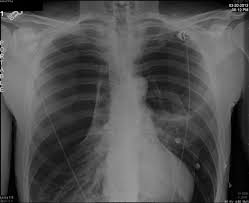

Emphysema is defined as abnormal, permanent enlargement of airspaces distal to the terminal bronchioles and accompanied by the destruction of airspace walls without obvious fibrosis.the main purpose of radiographs in emphysema patients is to exclude comorbidities such as pneumonia, pulmonary oedema, lung cancer, and so on.we are already well informed of the image findings of emphysema and. Can lung cancer be mistaken for copd? That's because the symptoms of emphysema can easily conceal copd, and copd can conceal the presence of lung cancer. Pancreatic cancer may be diagnosed as diabetes, due to the fact that diabetes is often a symptom or risk factor of pancreatic cancer. Malignant tumors trigger inflammation in surrounding normal lung tissue, and they may obstruct your airways and interfere with normal airflow.